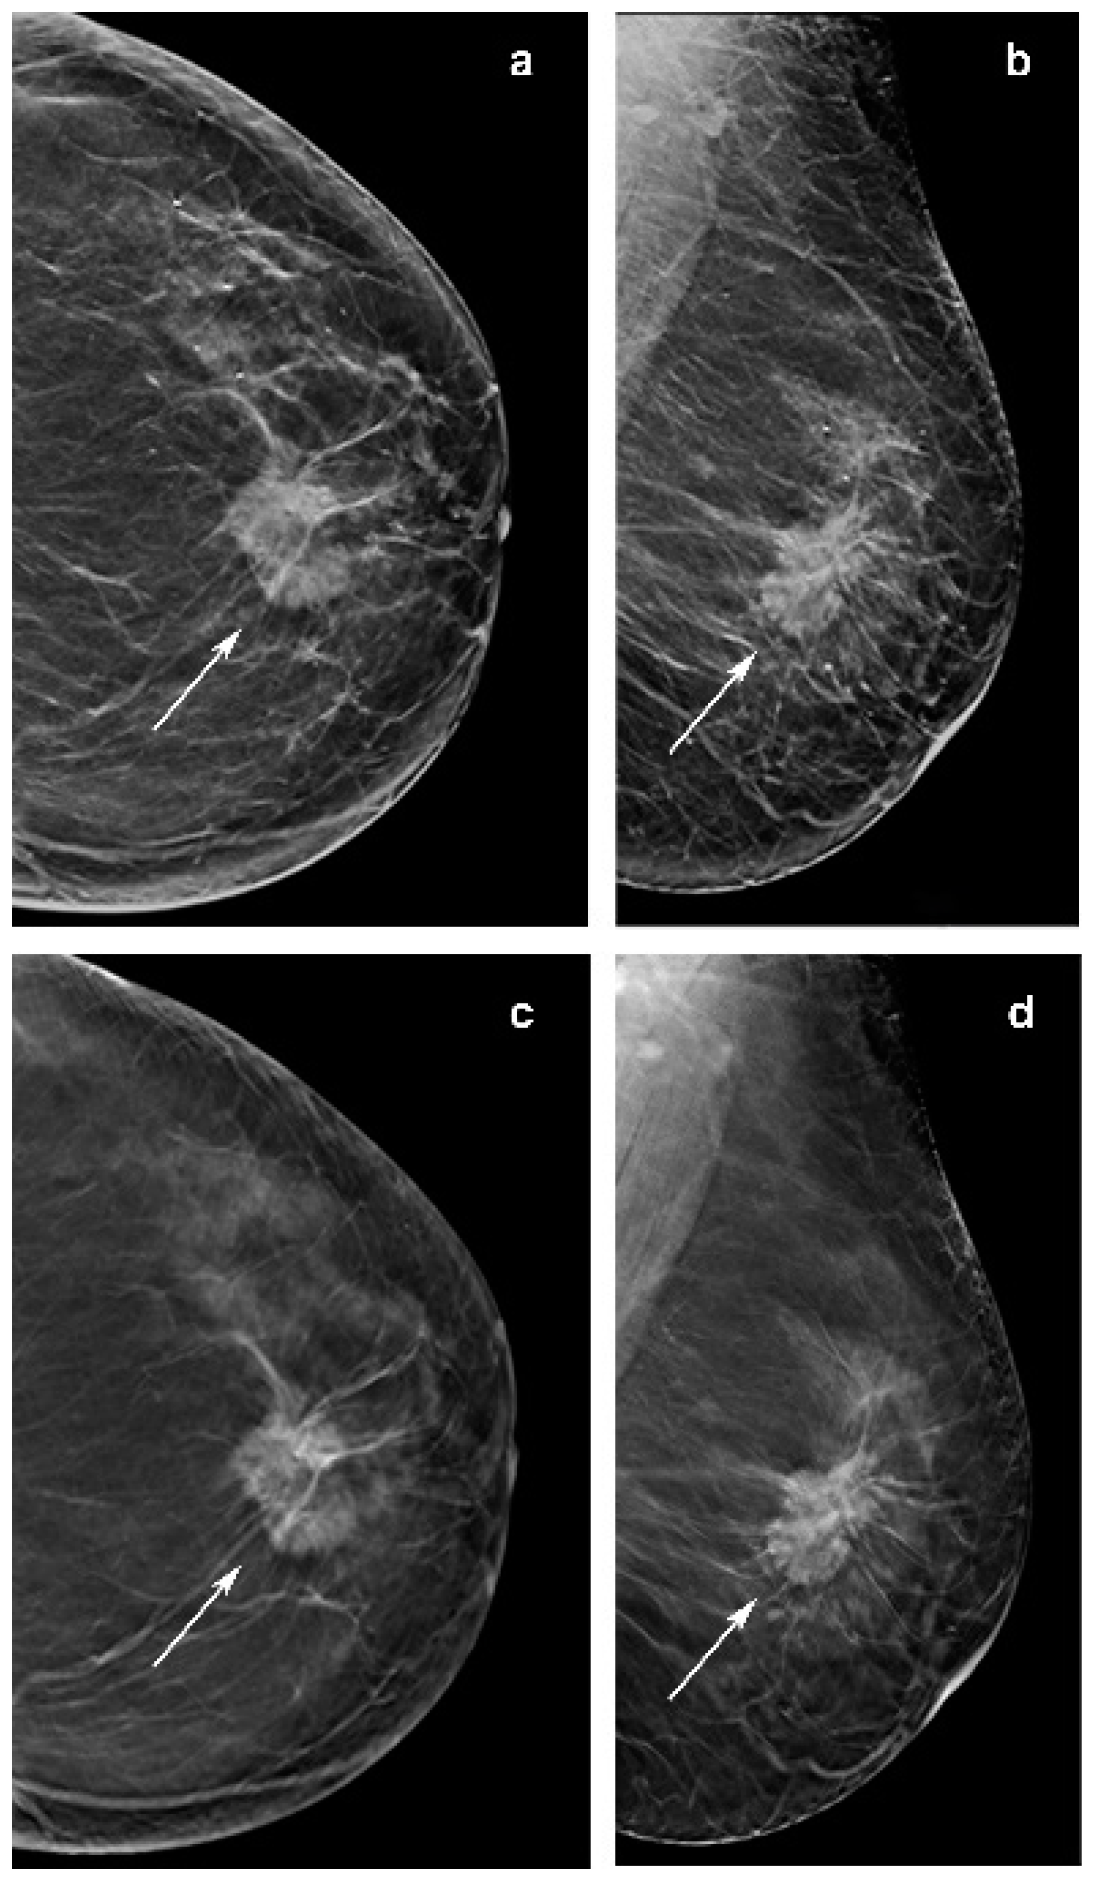

Figure 2.

Invasive lobular carcinoma presenting as a mass in a 57-year-woman, diagnosed at screening. (c,d) Craniocaudal and mediolateral oblique images of the right breast from slices of the DBT portion of the screening study demonstrate a poorly defined 7-mm mass in the outer superior quadrant (arrow). (a) It is less defined in the craniocaudal synthesized mammography (arrow head) and not visible in the mediolateral oblique synthetized mammography oblique image (b).

Other investigations reported that ILC is commonly presented as a mass on mammography. Of note, in our series 10/50 opacities were not recognized by at least one reader at synt2D but were visualized by all the readers at DBT. Two out of ten tumors with small diameter were identified in fatty breast only at DBT by all the readers (Figure 2). This could be explained by the better capabilities of DBT than synt2D in the evaluation of spiculated or ill-defined masses (Figure 3). Our results confirmed that calcifications with or without opacity due to their high density are easy to detect on both synt2D and DBT.